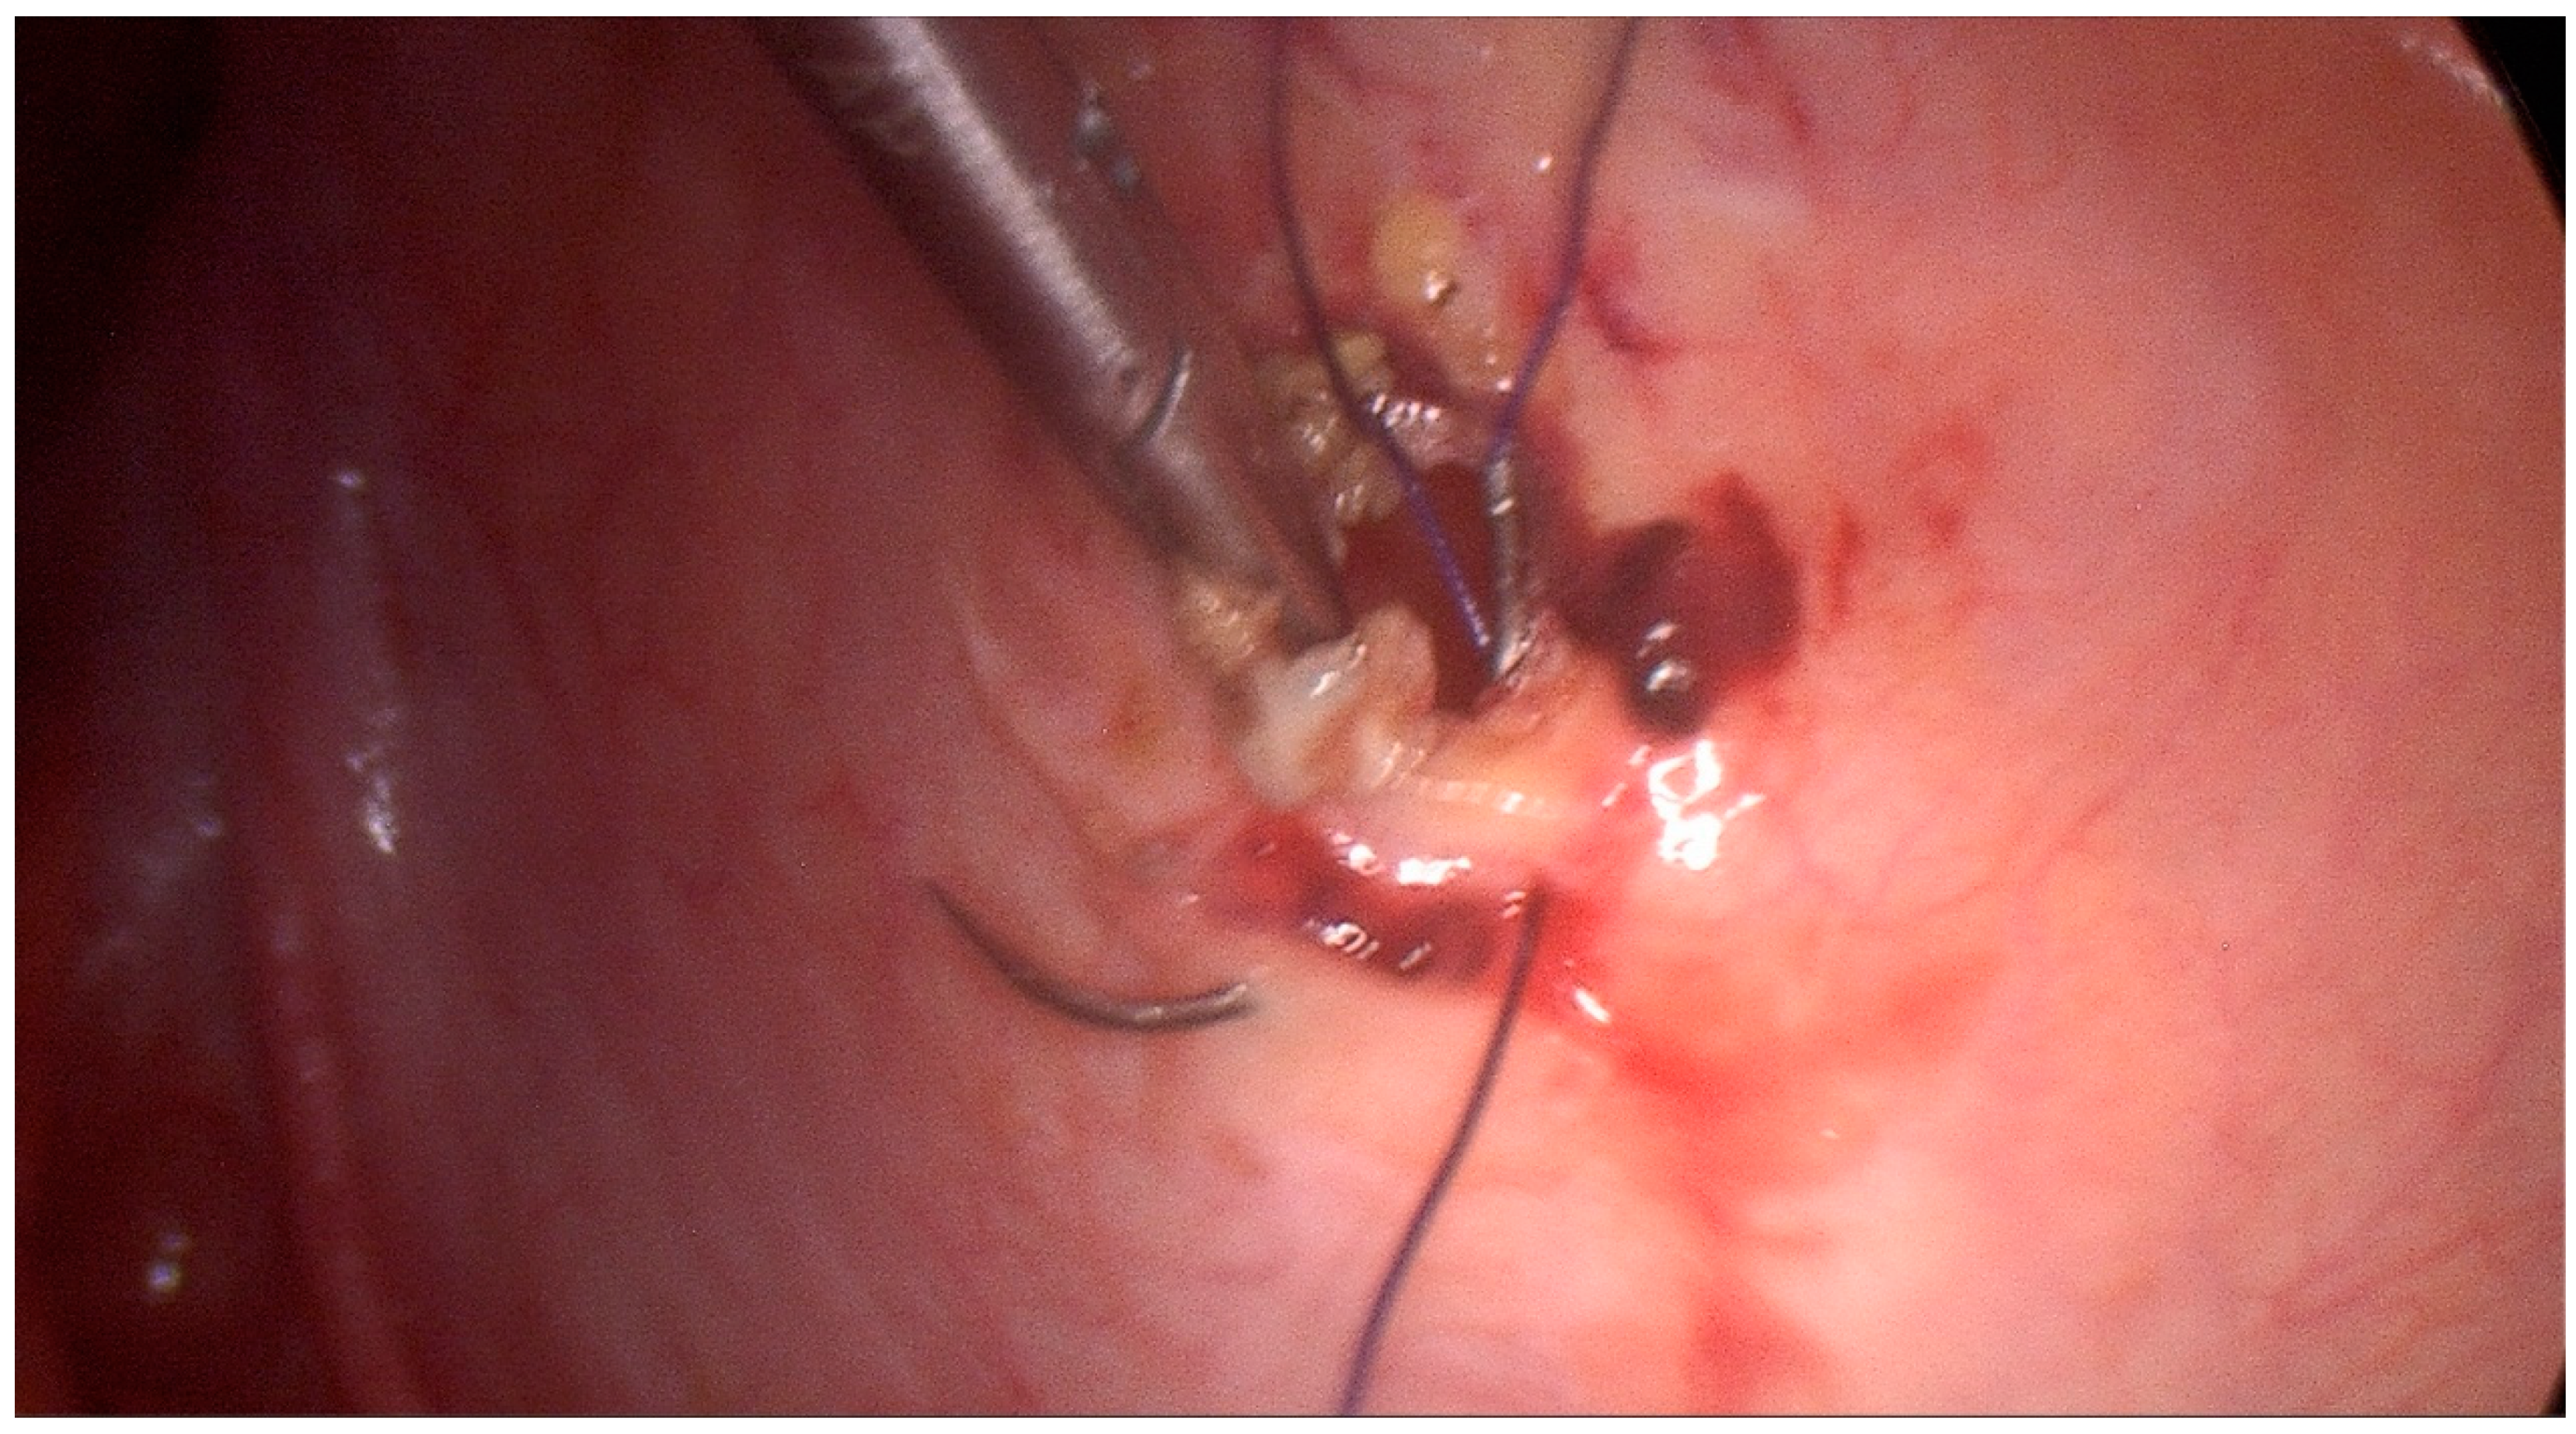

2. Case Description